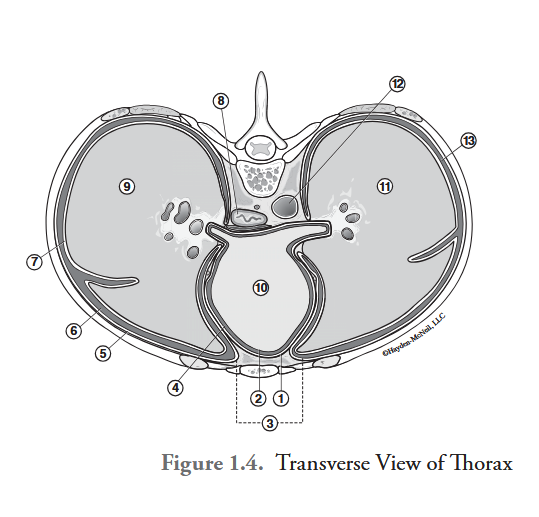

What is labeled #1?

parietal pericardium

What is labeled #2?

visceral pericardium (epicardium)

What is labeled #3?

mediastinum

What is labeled #4?

pericardial cavity

What is labeled #5?

parietal pleura

What is labeled #6?

right pleural cavity

What is labeled #7?

visceral pleura

What is labeled #8?

esophagus

What is labeled #9?

right lung

What is labeled #10?

heart

What is labeled #11?

left lung

What is labeled #12?

descending aorta

What is labeled #13?

left pleural cavity